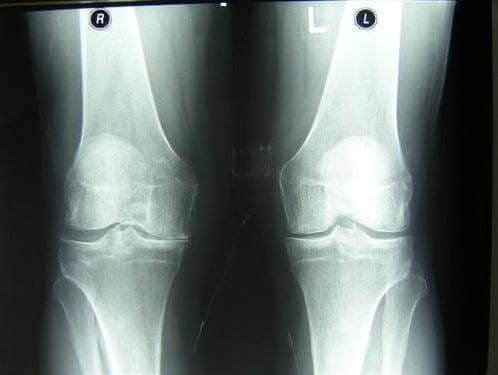

De exemplu, vă puteți uita la fotografiile realizate în spitale:

1. Articulația genunchiului unui pacient cu artroză (pacientul a folosit metodele "clasice" de tratament). Preparatele injectabile îi ușurau durerea pentru un timp scurt, dar nici întru-un caz nu au încetinit progresia bolii. Ca urmare, trebuia să-și ampută piciorul. Acum este persoană cu dizabilități.

Acestea sunt imagini ale articulațiilor "înainte" și "după" utilizarea HondroLife.